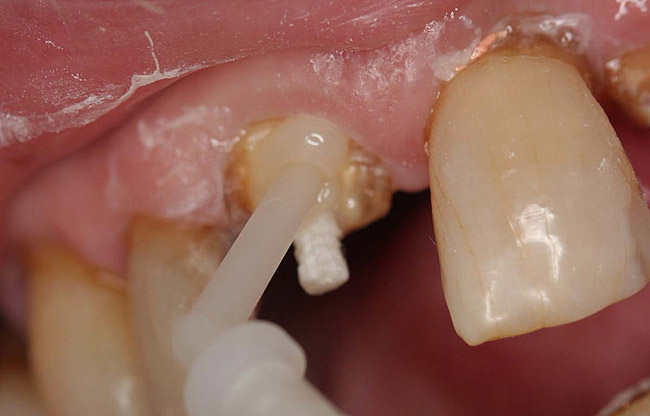

A Class IIIN maxillary left second molar required restoration (Figure 6). Four canals, a chamber space, and little cross section of tooth structure were in the gingival third. Gutta-percha was removed with a Peeso reamer supplied in the C-1 kit. The canal was shaped with a bur in the kit, which was the same size as the corresponding post (Figure 7). The tooth structure was bonded with Brush & Bond™ (Parkell, www.parkell.com), and then the resin cement was spun into the canal with a lenticulo spiral. A C-1 white post was placed in the palatal canals (Figure 8). The C-1 White Post is a fiber-reinforced composite post, which flexes at the same rate as dentin to minimize root stresses.

Figure 7  Second molar with the palatal canal prepared for post placement.

Figure 7